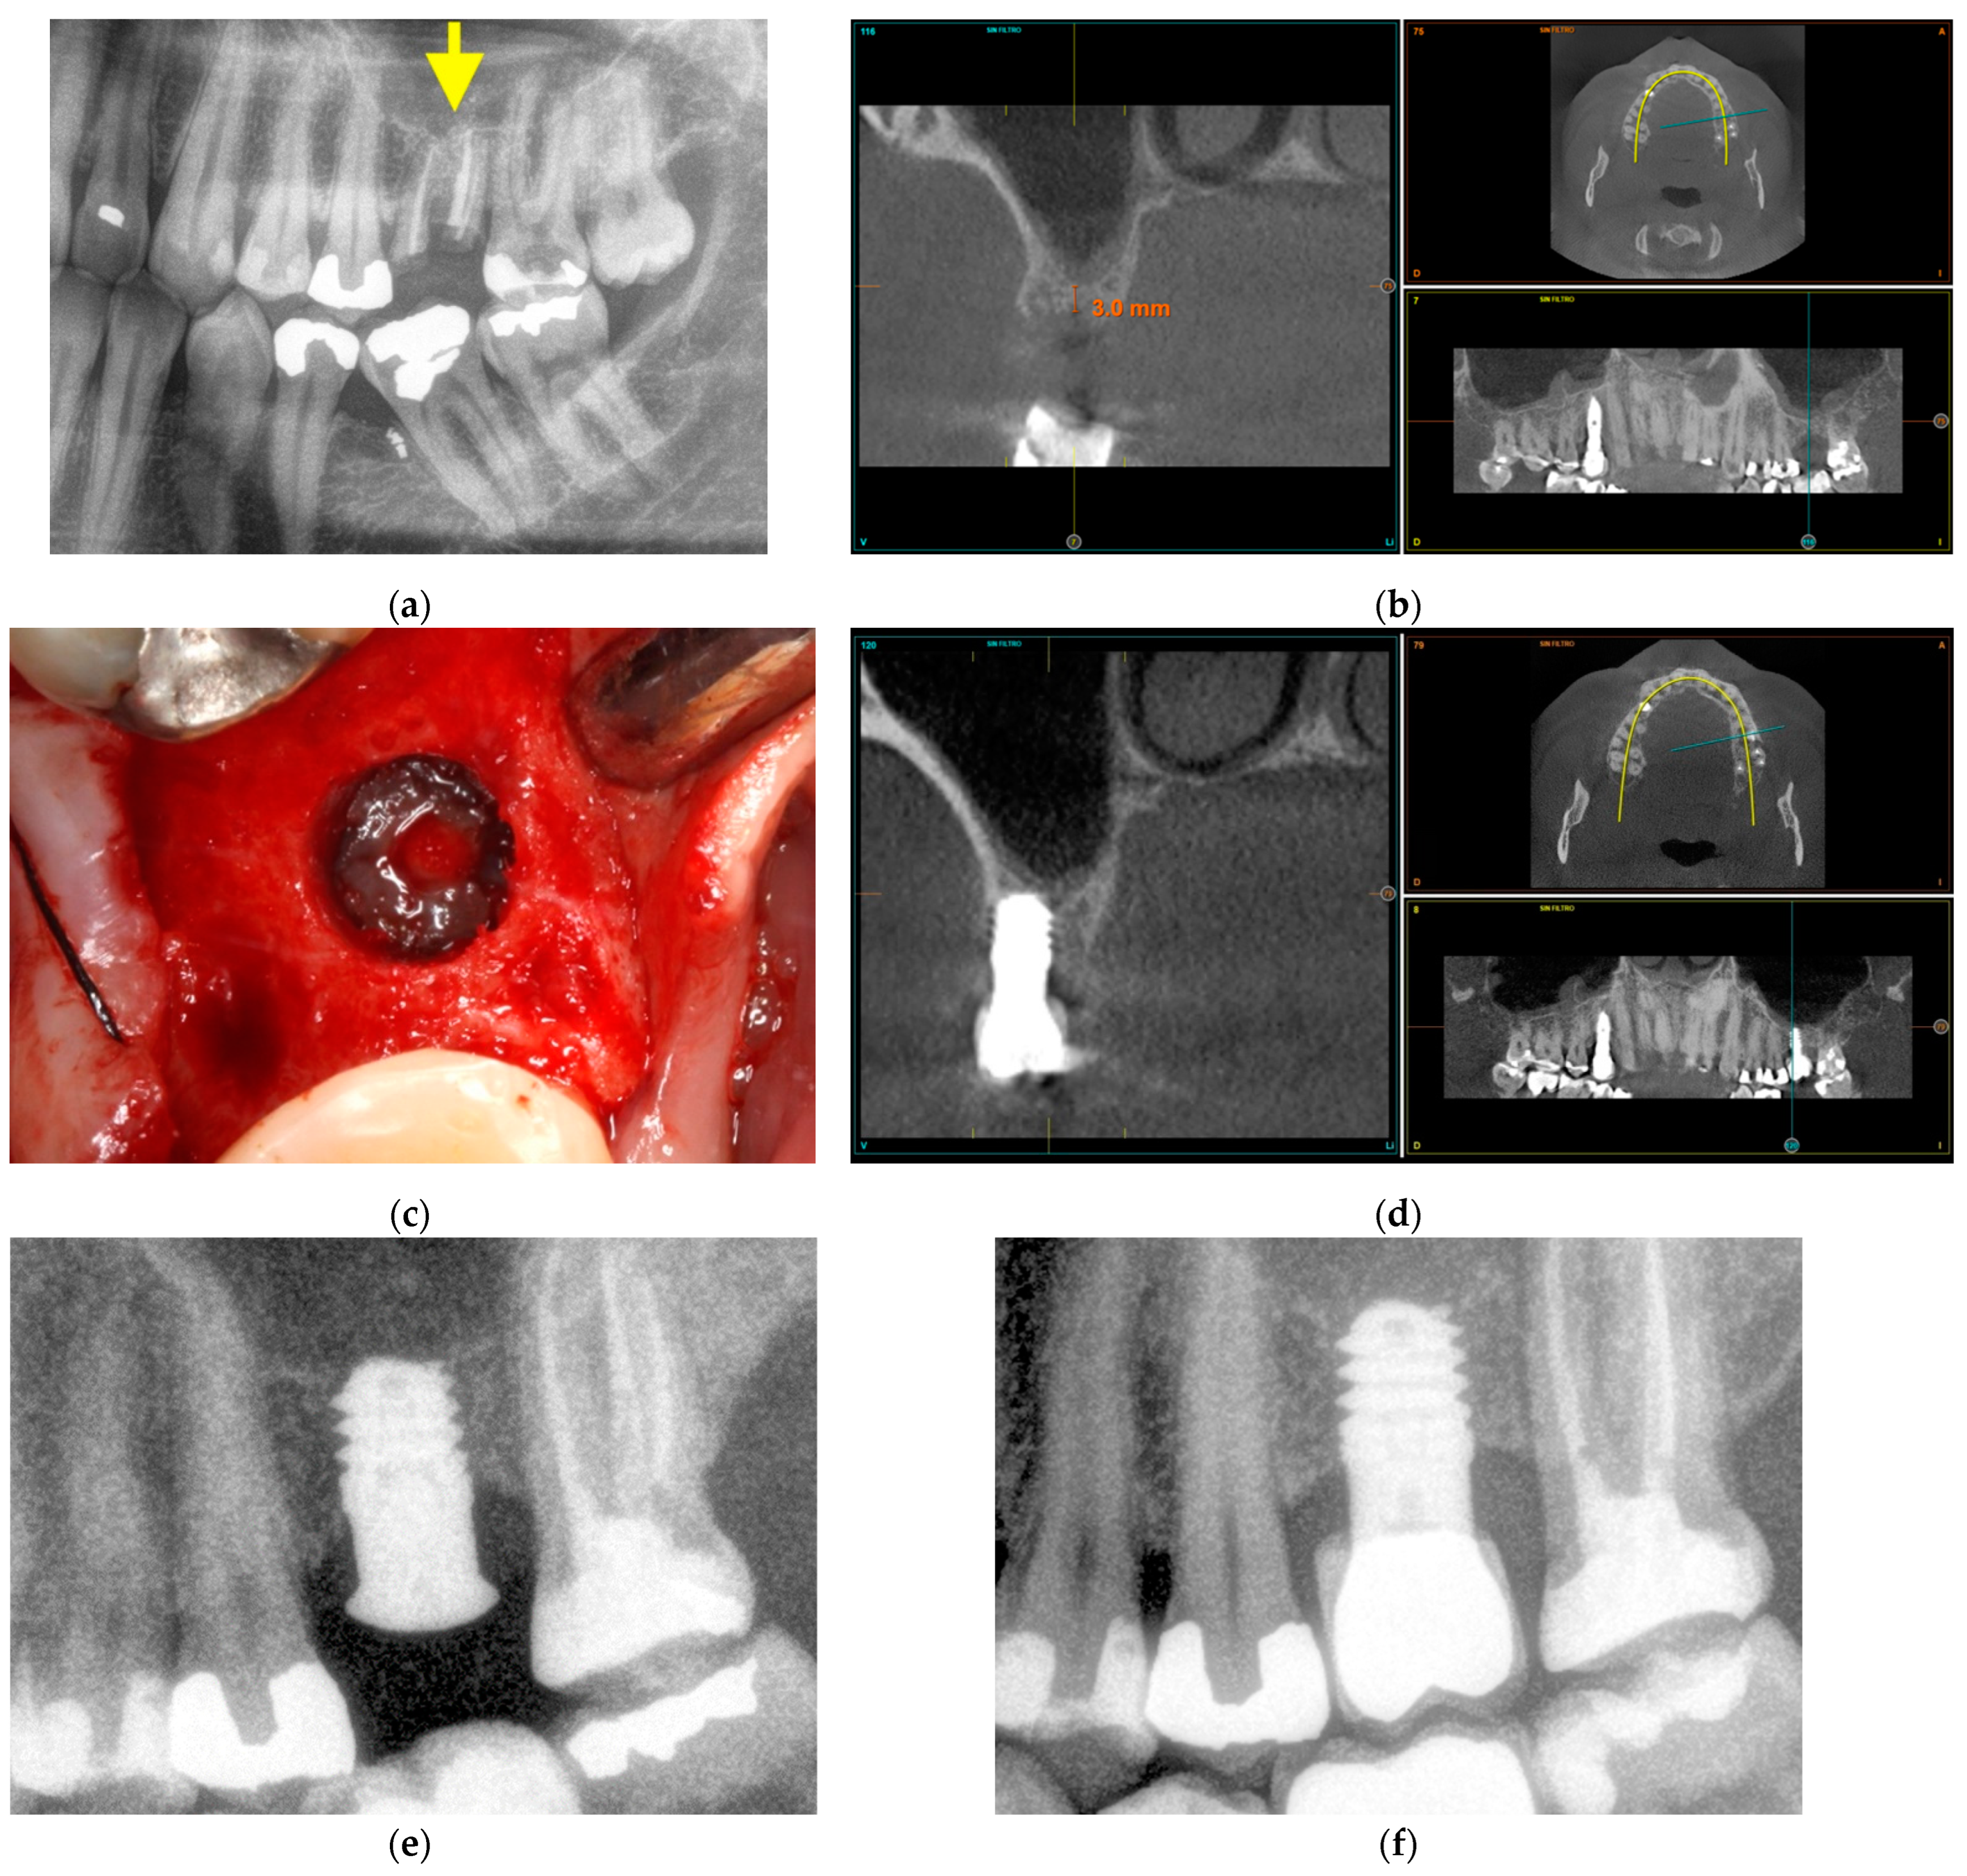

3.3.2. Maxillary Sinus Floor Augmentation

The second case corresponds to an upper jaw with severe vertical bone resorption (Figure 8). The tooth roots were removed due to infection (Figure 8a), and the site was filled with PRGF-Endoret®. After three months, the available vertical height was 3 mm (Figure 8b). In the surgery plan, the bone density of the site was measured, and an extra short unicCa® implant 5.5 mm in length was planned. The surgery was carried out with a frontal attack drill (Figure 8c) up to the sinus membrane. The membrane is lifted gently with autologous bone from the osteotomy mixed with PRGF-Endoret® and retained in position after the positioning of the implant (Figure 8d,e). Soon after the surgery, the peri-implant bone height was 4.5 mm. Five years after the surgery, the bone height was stable around the implant and in its apical part (Figure 8f). The new vertical bone height was 7.5 mm.

Figure 8.

Maxillary sinus floor augmentation. Prior extraction of the infected tooth roots, marked with a yellow arrow (a). Three months after extraction, the residual bone height is 3 mm (b). The sinus membrane was gently pushed upwards with autologous bone recovered from the site preparation mixed with PRGF-Endoret® (c). A 5.5 mm short implant is placed at the implant site to support the sinus floor elevation apically (d). Three months after implant placement, the bone height around the implant was 4.5 mm (e). Five years after the placement of a short implant, the measured bone height at the implant site was 7.5 mm (f).